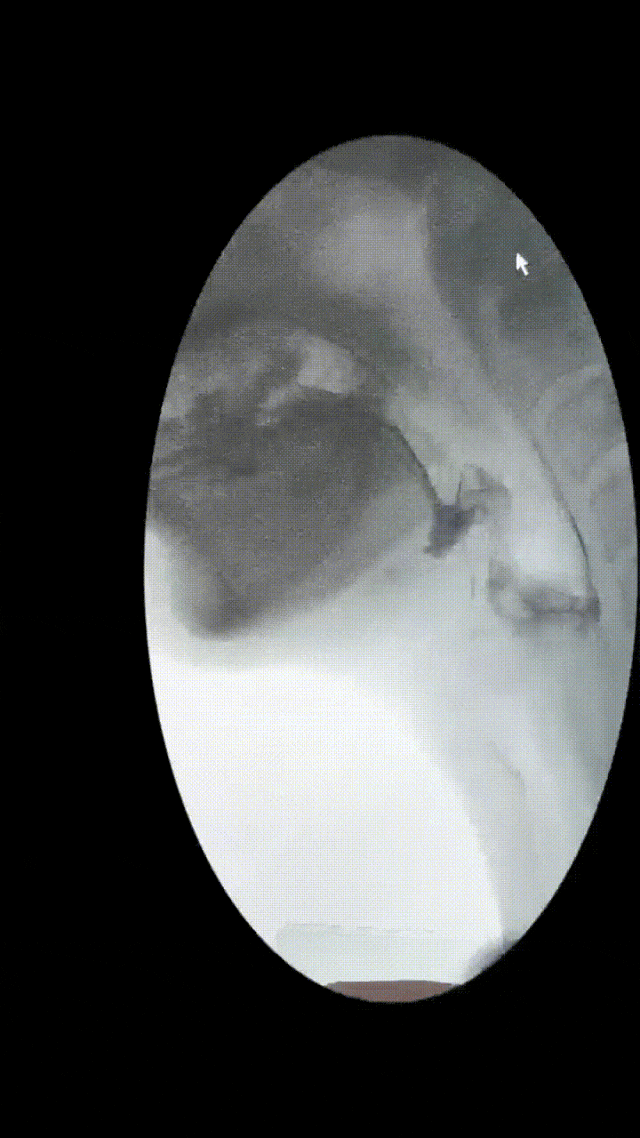

通过吞咽造影检查,李先生的问题终于“水落石穿”——是“吞咽障碍”惹的祸!

在精准评估方面,可以通过“洼田饮水试验”快速判断风险等级;同时,借助仪器检查——吞咽造影造影(VFSS)、喉内镜(FEES)精准定位功能障碍环节。

▲李先生存在环咽肌开放不完全,会厌谷和梨状窦大量残留,并且存在明显误吸,因此导致反复重症肺部感染。